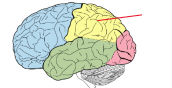

lobus frontalis

lobus parietalis

lobus occipitalis

lobus temporalis

insula

gyrus precentralis

gyrus postcentralis

sulcus centralis

sulcus lateralis